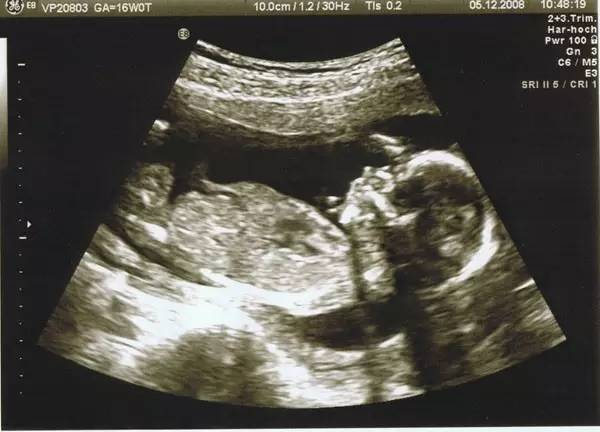

孕16周的胎宝宝↑↑↑,完美的全身照

告诉你一个小秘密,如果你想保留一张宝宝的全身B超照,要注意选择时间。早于15周,画面里宝宝太小;大于16周,画面里又放不下宝宝。所以最好选在15~16周。